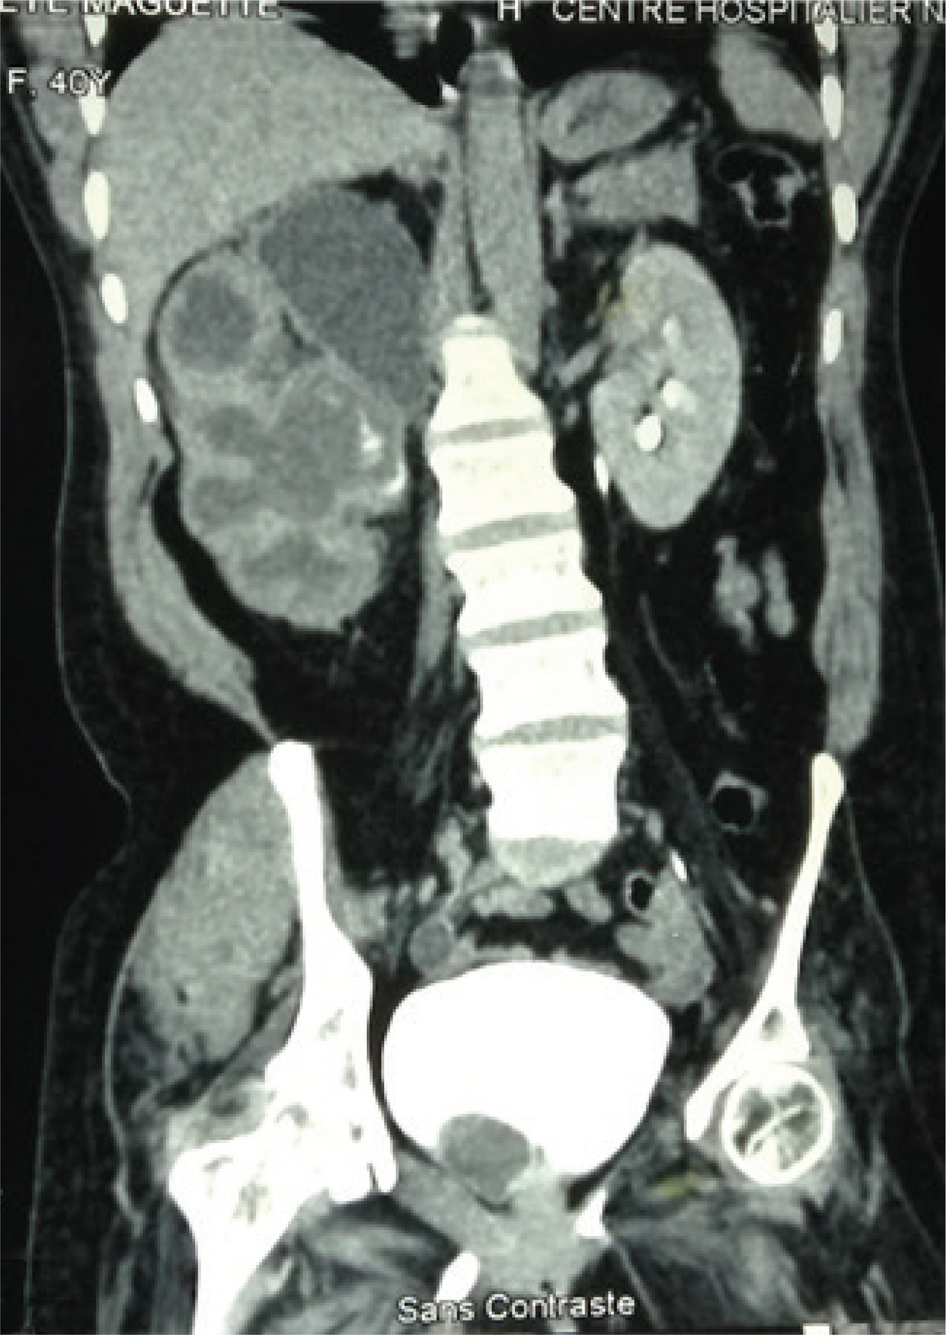

Fig 2

Figure 2: A contrast CT-scan showing a cystic right renal tumor in the upper pole with associated hydronephrosis. Courtesy: Grand Yoff Hospital.

CT-scan or MRI findings of cystic renal lesion, Bosniak class I and class II, have minimum risk of malignancy and require no follow-up. However, Bosniak class IIF has a 10% risk of malignancy and follow-up with ultrasound or CT is recommended. Bosniak class III and IV have 65% and 92% risk of malignancy respectively and require treatment (Figure 2) (9).